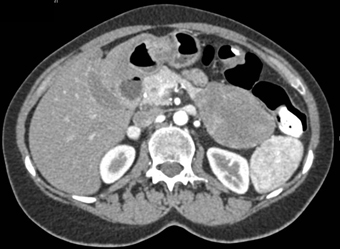

In this patient referred for a pancreatic mass the final dx was?

CTisus Quiz   CTisus Quiz

neuroendocrine tumor pancreas

adrenal carcinoma

GIST tumor

SPEN tumor